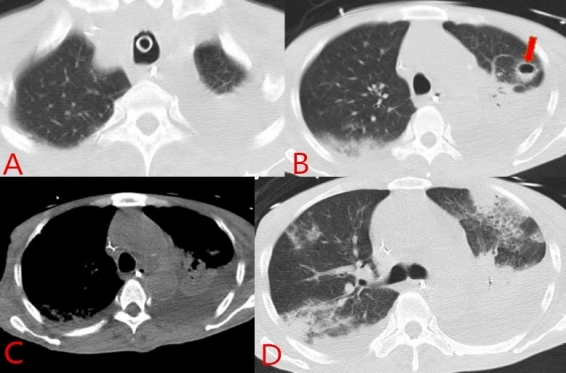

考虑短期内无拔管指征,患者入院第12天予气管切开,继续机械通气支持。经上述治疗,患者氧和进一步改善,痰液明显减少,炎症指标下降趋势,体温基本正常,心功能基本稳定,故于入院第16天开始行脱机锻炼。入院第18天复查胸部CT,提示两肺渗出及两侧胸腔积液均进展,左上肺新发病灶(图 3),予胸腔穿刺置管引流,胸水提示渗出液,培养阴性。尽管肺部影像学没有明显好转,但临床症状和炎症指标明显好转,入院第20天停用头孢他啶/阿维巴坦钠(使用1周),改为头孢哌酮钠/舒巴坦钠(2 g, /8h)。患者于入院第20天(2022-06-04)脱机成功,观察4 d后,病情平稳而转入呼吸科普通病房继续治疗。入普通病房后,在康复治疗师指导下,已能下地短暂站立。患者于入院第38天(2022-06-22),转入康复医院继续康复以及功能锻炼等治疗。

| 图 3 入院第18天(2022-06-02)胸部CT:A:两肺渗出均进展;B:箭头所指为左上肺新发病灶;C:两侧胸腔积液较前进展;D:两肺多发渗出、实变 |